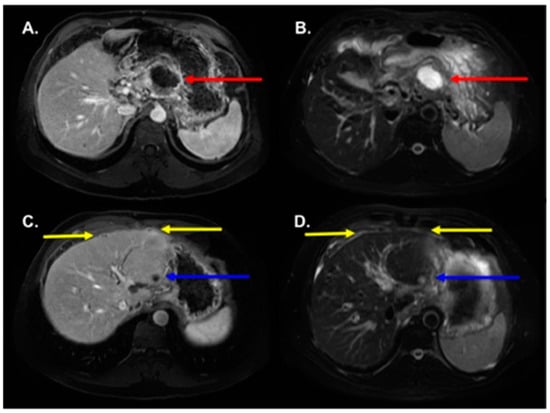

3.2. MRI Findings